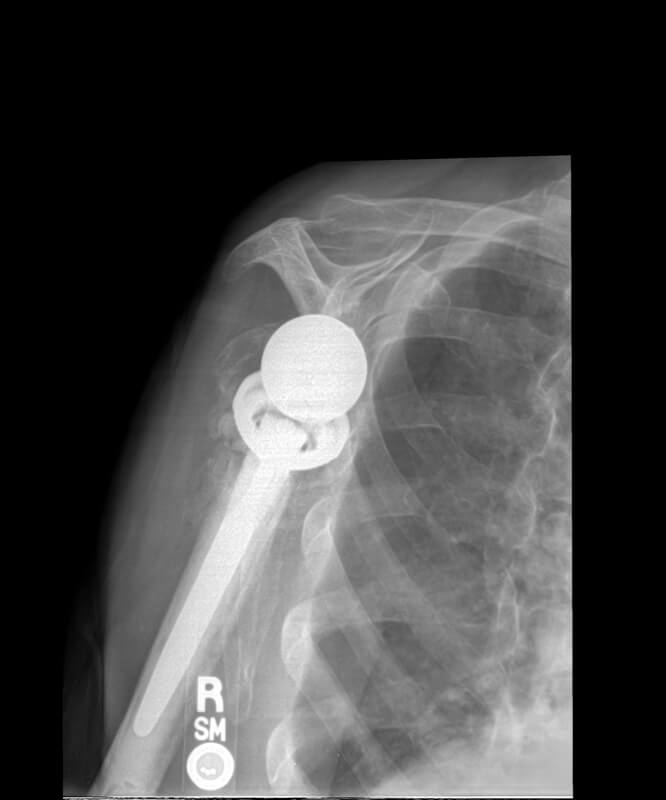

Stryker/Wright/Tornier, Aequalis Fracture